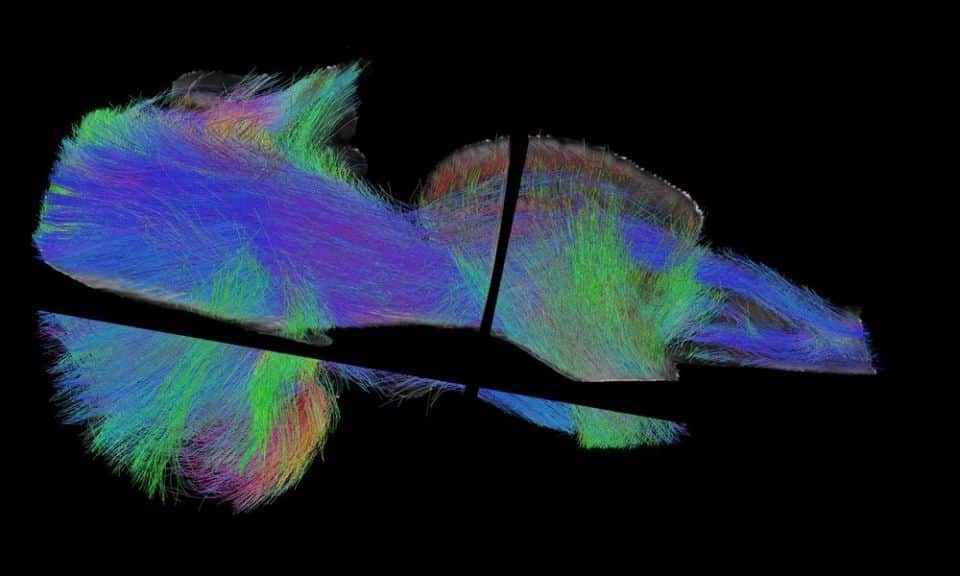

Μια νέα, άγνωστη μέχρι σήμερα περιοχή στον ανθρώπινο εγκέφαλο ανακάλυψε ο ελληνικής καταγωγής “χαρτογράφος εγκεφάλου” Γιώργος Παξινός. Η περιοχή βρίσκεται κοντά στο σημείο όπου ενώνεται ο εγκέφαλος με το νωτιαίο μυελό, μέσα στο κάτω παρεγκεφαλιδικό σκέλος, μια περιοχή που ενσωματώνει και συνδυάζει τις αισθητηριακές και τις κινητικές πληροφορίες προκειμένου να διορθώσει τη στάση του σώματος, την ισορροπία του και τις μικρές επιδέξιες κινήσεις και την ονόμασε «Ενδοσχοινιοειδή Πυρήνα»(Endorestiform Nucleus).

“Τώρα που έχει χαρτογραφηθεί, θα είναι δυνατό να μελετηθεί από την ευρύτερη ερευνητική κοινότητα, ενώ μένει να προσδιορισθεί η λειτουργία αυτής της νεοανακαλυφθείσας περιοχής του εγκεφάλου”. Σύμφωνα με τον κύριο Παξινό, «το κάτω παρεγκεφαλιδικό σκέλος, που ονομάζεται επίσης σχοινιοειδές σώμα, είναι σαν ένα ποτάμι που μεταφέρει πληροφορίες από το νωτιαίο μυελό και το εγκεφαλικό στέλεχος προς την παρεγκεφαλίδα. Η περιοχή του εγκεφάλου που τώρα ανακαλύφθηκε, είναι μια ομάδα νευρώνων μέσα σε αυτό το σκέλος, εξ ου και το όνομά της «ενδοσχοινιοειδής πυρήνας».

Οι νευρώνες αυτοί είναι σαν ένα νησί μέσα στο ποτάμι, έτσι αυτός ο πυρήνας βρίσκεται σε προνομιούχα θέση για να λαμβάνει εισροές από το νωτιαίο μυελό. Το κάτω παρεγκεφαλιδικό σκέλος είναι μια μεγάλη δέσμη νευραξόνων και ο ενδοσχοινιοειδής πυρήνας είναι μια ομάδα νευρώνων ενσωματωμένη μέσα σε αυτή τη δέσμη. Η περιοχή αυτού του εγκεφάλου “με κοιτάζει’ εδώ και χρόνια “που μελετώ τον εγκέφαλο, στην πραγματικότητα είναι σαν εκείνη να με ανακάλυψε και όχι εγώ αυτή!